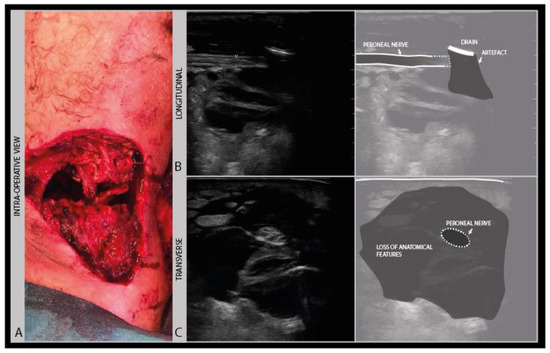

In recent wounds, stitches, surgical staples and drains may be still in place, that are usually echodense and scatter soundwaves from the surface, thereby limiting visual access to the underlying nerve (Figure 11).

Figure 11.

Severe knee torsion injury with a large tissue defect (A): post-surgical debridement ultrasound image of the posterior knee, with a tissue drain artefact obscuring the view of the underlying peroneal nerve (B) and a loss of anatomical features (C).

Ultrasound of fresh wound areas may be complicated by hematoma, giving a diffuse grayish shadowing of the image (Figure 12), and a loss of recognizable anatomical features (Figure 11 B).